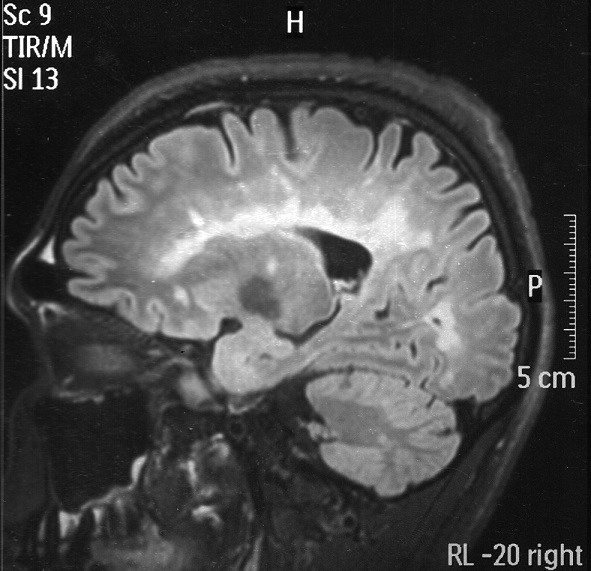

Al hacerle el examen, el paciente estaba lúcido, orientado en las tres esferas, con velocidad de procesamiento de información disminuida, memoria inmediata alterada y disartria escandida. Presentaba paresia de músculo recto externo derecho, nistagmus vertical y horizontal, hemiparesia derecha (4/5) de predominio crural, espasticidad en miembro inferior derecho, atrofia en antebrazo derecho (secuelar), hiperreflexia en miembros inferiores, clonus y signo de Babinski bilateral. La sensibilidad superficial y profunda estaba disminuida en cuatro extremidades, no se evidenció nivel sensitivo. Se encontró marcha atáxica, y ataxia de extremidades de predominio derecho. El puntaje de la Escala Expandida del Estado de Discapacidad (EDSS) fue de 6,5. La resonancia magnética (RM) del encéfalo sin contraste mostró múltiples lesiones desmielinizantes supra e infratentoriales, periventriculares, yuxtacorticales, en mesencéfalo, protuberancia y bulbo, pedúnculos cerebelosos y hemisferio cerebeloso derecho, además de leve disminución del parénquima cerebral (figura 1).

Posteriormente, en un estudio de RM con gadolinio se logró evidenciar que algunas de las lesiones anteriormente descritas captaban el contraste (imágenes no disponibles, descritas en historia clínica); así tambien, en la RM de la columna cervical se observaron dos lesiones hiperintensas en el nivel C4 y T2, en cordones laterales, que no captan contraste. En el análsis de líquido se evidenciaron bandas oligoclonales positivas. El ANA y el ANCA fueron negativos. Se estableció el diagnóstico de EMPP, ya que cumplió con los criterios de McDonald 2017 (5).